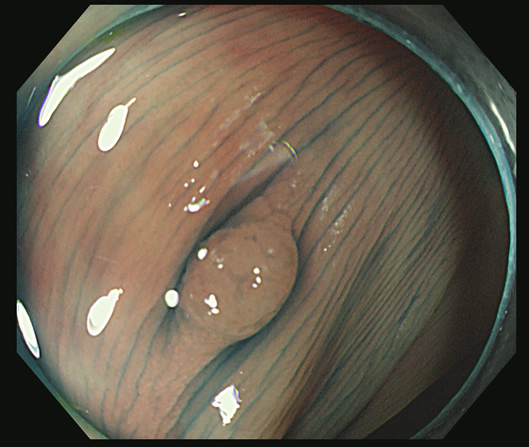

CSDPの除去

ポリープの切除創に、見られる白い突起は「CSDP」と呼ばれます。成分は結合組織で、粘膜成分(腫瘍)は、通常は含まれません。

しかし、稀に、粘膜成分が残存することがあります。これを確実に除去することが再発(内視鏡後・大腸癌)の予防に肝要です。

スネアー・ワイヤーで病変を大きく切除します

周囲の正常粘膜を含んだまま「目玉焼き」状に切除されます

一見、完全切除のように見えますが・・・